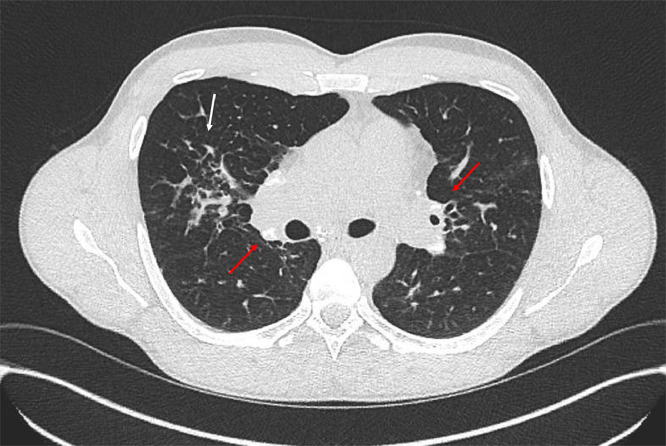

结节病是一种病因不明的复杂疾病,主要累及肺部,但可累及几乎任何器官。由于缺乏特异性标记物,诊断具有挑战性,需要评估临床特征,仔细成像,排除其他条件,理想情况下,组织活检显示非坏死性肉芽肿。超过90%的患者肺部受累,表现为干咳和呼吸困难等症状,以及发烧和体重减轻等全身症状。约30%的病例出现肺外表现,可影响任何器官,包括心脏、神经系统和眼睛。治疗涉及多学科方法,一些患者需要免疫抑制和抗纤维化治疗。尽管通常预后良好,但结节病可导致显著的发病率和死亡率,特别是肺部和心脏并发症。英夫利昔单抗(infliximab)和尼达尼布(nintedanib)等新兴疗法为难治性病例带来了希望,尽管它们存在严重感染和其他副作用的风险。

Sarcoidosis is a complex disease of unknown origin, primarily affecting the lungs but capable of involving almost any organ. Diagnosis is challenging due to the lack of specific markers and requires assessment of clinical features, careful imaging, exclusion of other conditions and, ideally, a tissue biopsy demonstrating non-necrotising granulomas. Over 90% of patients have pulmonary involvement, presenting with symptoms like dry cough and breathlessness, along with systemic signs such as fever and weight loss. Extrapulmonary manifestations occur in about 30% of cases and can affect any organ, including the heart, nervous system and eyes. Management involves a multidisciplinary approach with some patients requiring immunosuppressive and antifibrotic therapies. Despite generally good outcomes, sarcoidosis can lead to significant morbidity and mortality, particularly from pulmonary and cardiac complications. Emerging treatments like infliximab and nintedanib offer hope for refractory cases, although they carry risks of serious infections and other side effects.